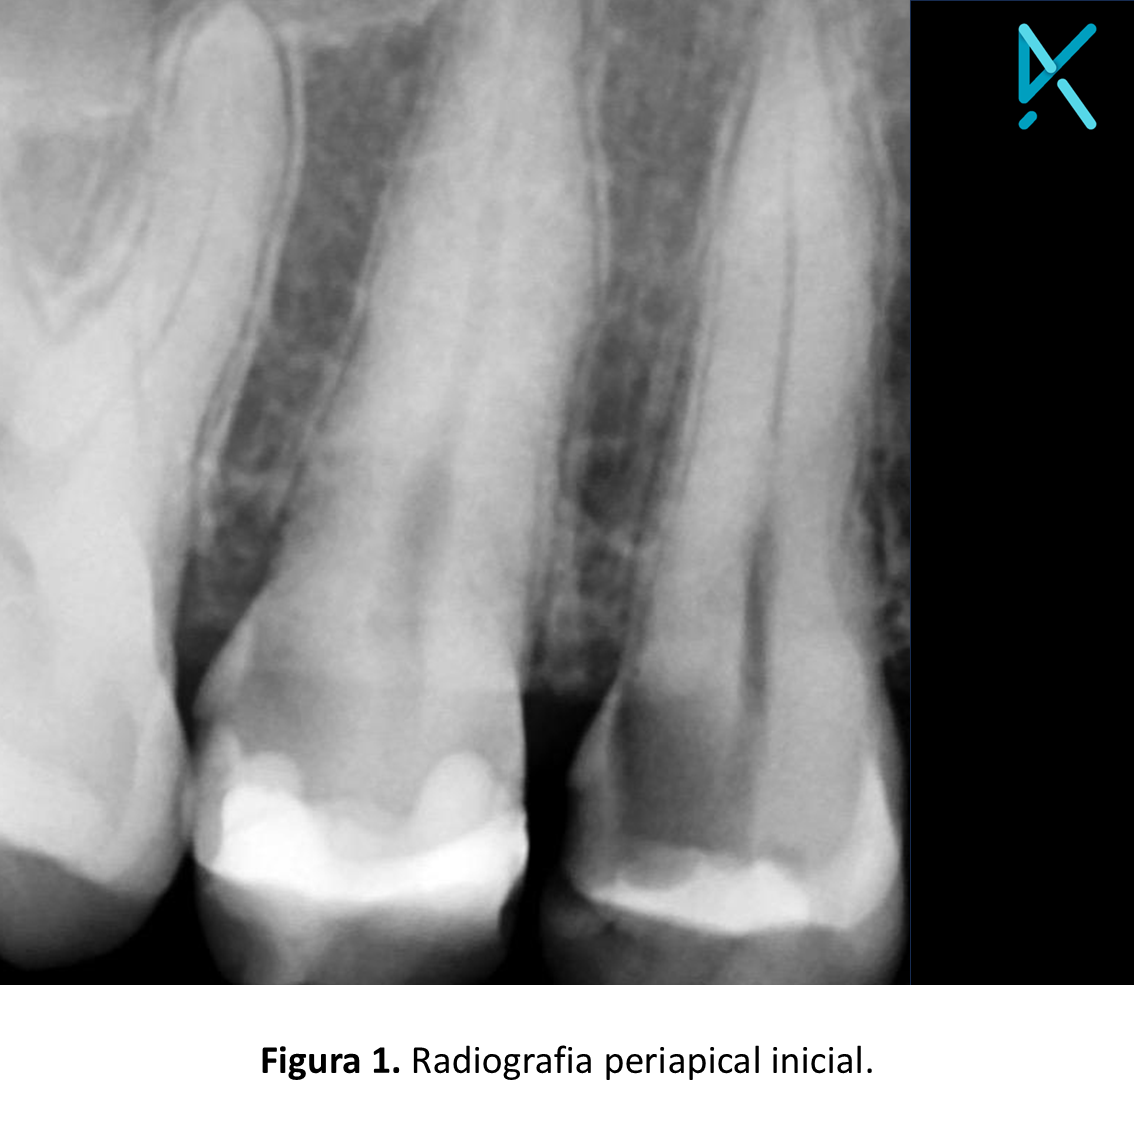

Na radiografia periapical inicial, foi possível observar uma cárie extensa envolvendo as faces distal e oclusal. A endodontia foi realizada em sessão única, e a blindagem da cavidade de acesso, juntamente com a restauração total do elemento, foi realizada com a resina Stela, da SDI, uma vez que a técnica é rápida e de fácil execução.